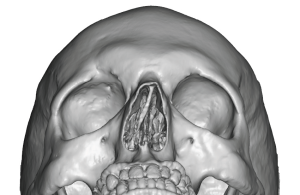

Typical Male Aesthetic Goals

Unlike full feminization procedures, male brow reduction often aims to:

- soften the ridge

- reduce central bossing

- maintain a natural masculine brow projection